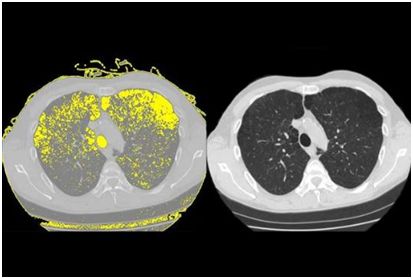

3.HIV 治疗的背后:HIV 如何一步步将患者的肺摧毁!

高达 30%的接受抗逆转录病毒疗法治疗的艾滋病毒患者发展为慢性肺病肺气肿。 Weill Cornell 医学研究人员的新研究发现了一种可能解释为什么会发生肺损伤的机制。

研究人员在“细胞报告”5 月 9 日发表的研究报告中显示,人类免疫缺陷病毒或 HIV 与干细胞结合,称为基底细胞,其转化为其他类型的细胞。该过程重新编程基底细胞,导致它们释放被称为蛋白酶的酶,其可以破坏肺组织并在进行氧气交换的空气囊的壁中戳出孔。

为了进行这项研究,调查人员将正常的人气道基底细胞从健康非吸烟者的肺部收集,并在观察下暴露于艾滋病毒一段时间。将病毒与基底细胞表面结合并重新编程,以开始产生可以分解蛋白质并破坏组织的酶或蛋白酶,称为金属蛋白酶 -9。因为研究人员知道肺气肿是气道疾病,这一发现表明,当基底细胞呈现称为“破坏性表型”的晶型时,他们开始在健康组织中消失,这会及时得导致肺气肿。